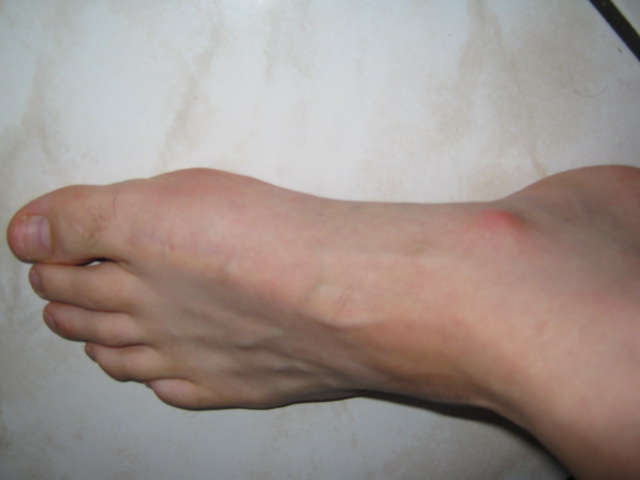

J'ai une excroissance au niveau du pied gauche qui est apparue à l'utilisation.

Après différents examens (radio et écho), il a été mis en évidence que la bosse au niveau de mon Scaphoïde gauche (voir photos) est dut à un échauffement du pied au contact de la zone d’ancrage de la bride supérieure. Cet échauffement se répète à chaque coupe de pied.

Cela est très douloureux et genant. Cela devient pénible de faire une sortie de vélo.